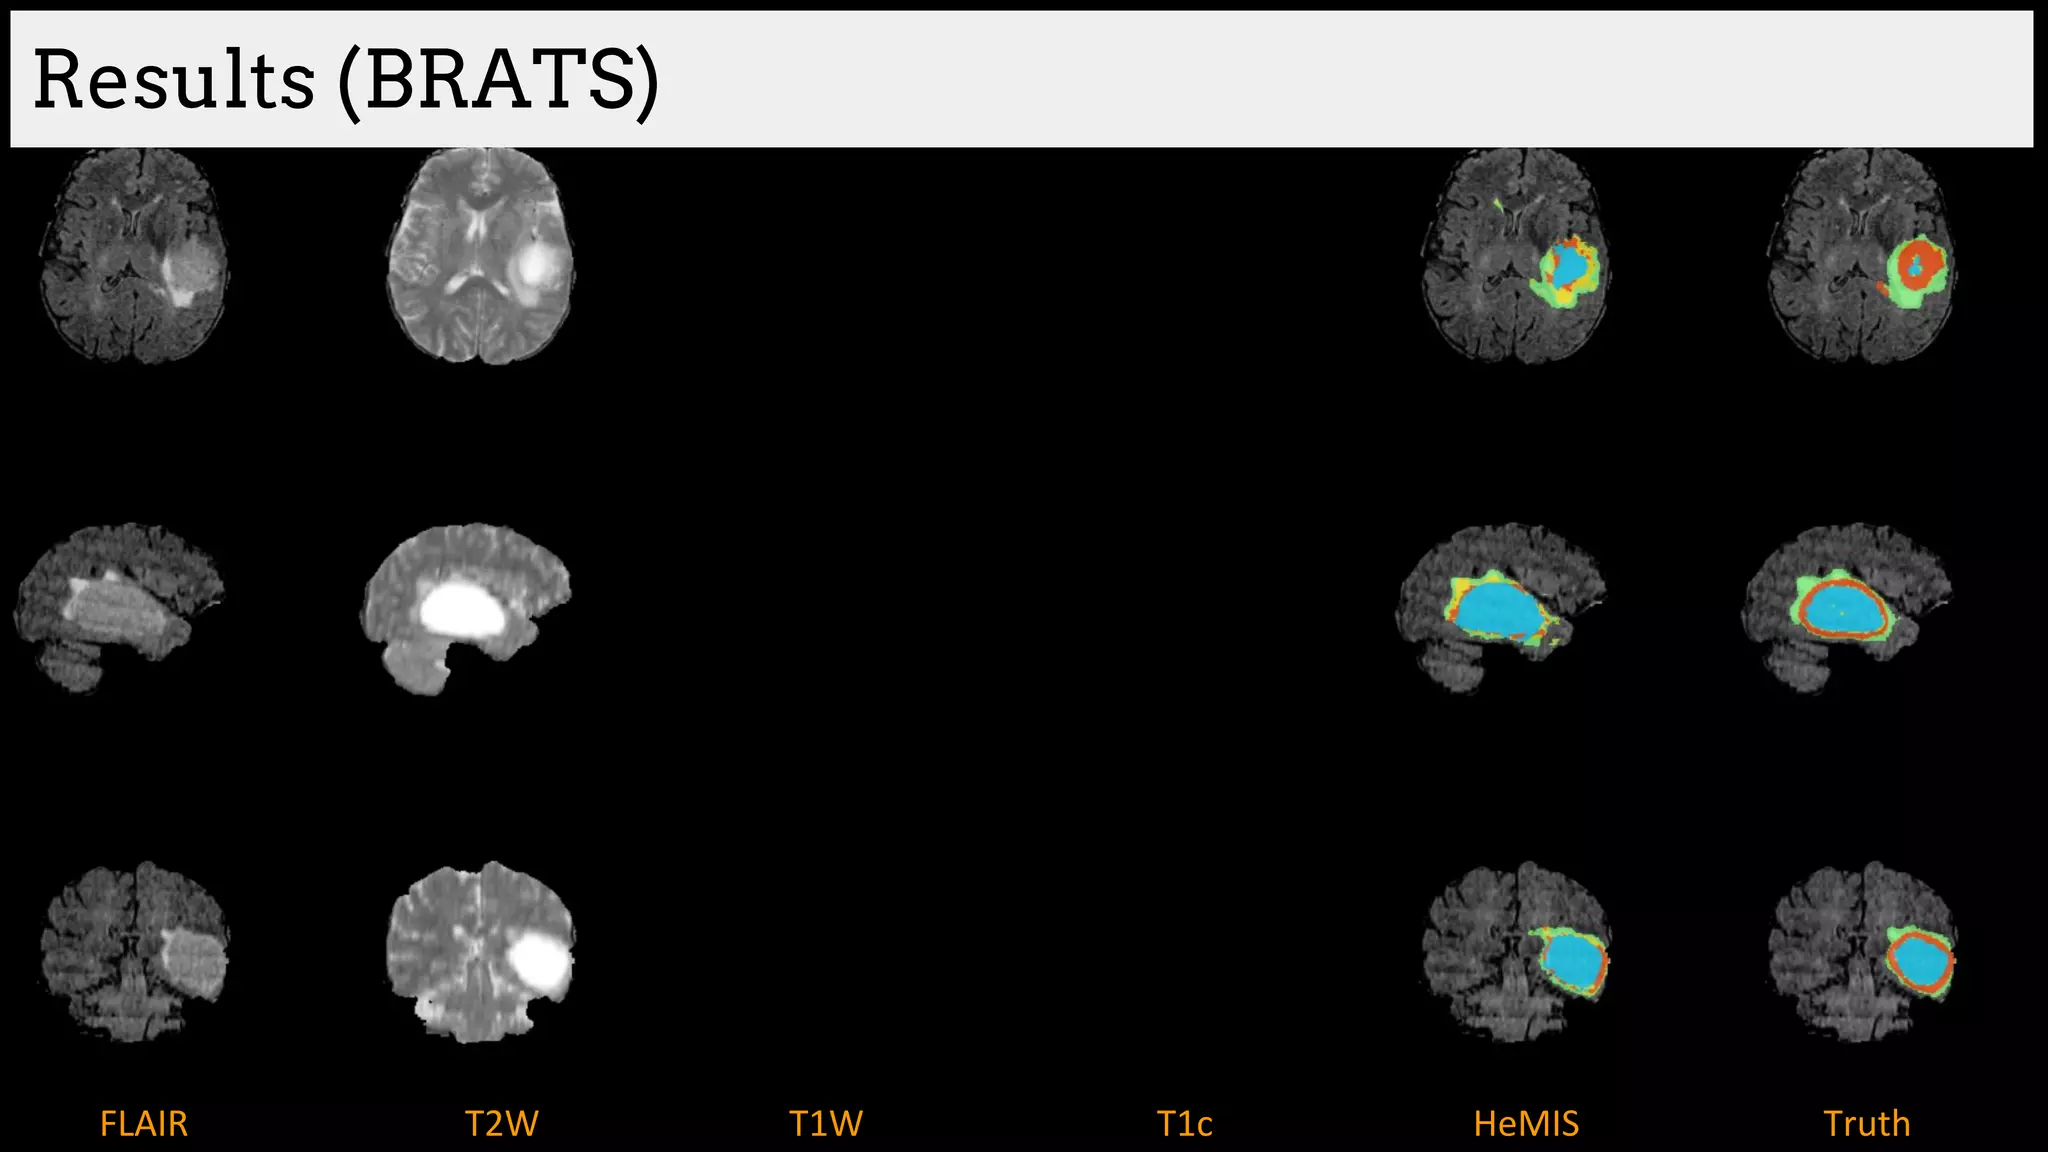

Results (BRATS)

Brain tumor segmentation (BRATS2013 dataset)

T1 T2

T1C Flair

GT

Edema

Necrosis

Non-enhanced

Enhanced

Training data:

220 subjects with high grade and

54 subjects with low grade tumors

Dice Similarity

[Havaei et al. HeMIS: Hetero-Modal Image Segmentation, MICCAI 2016]